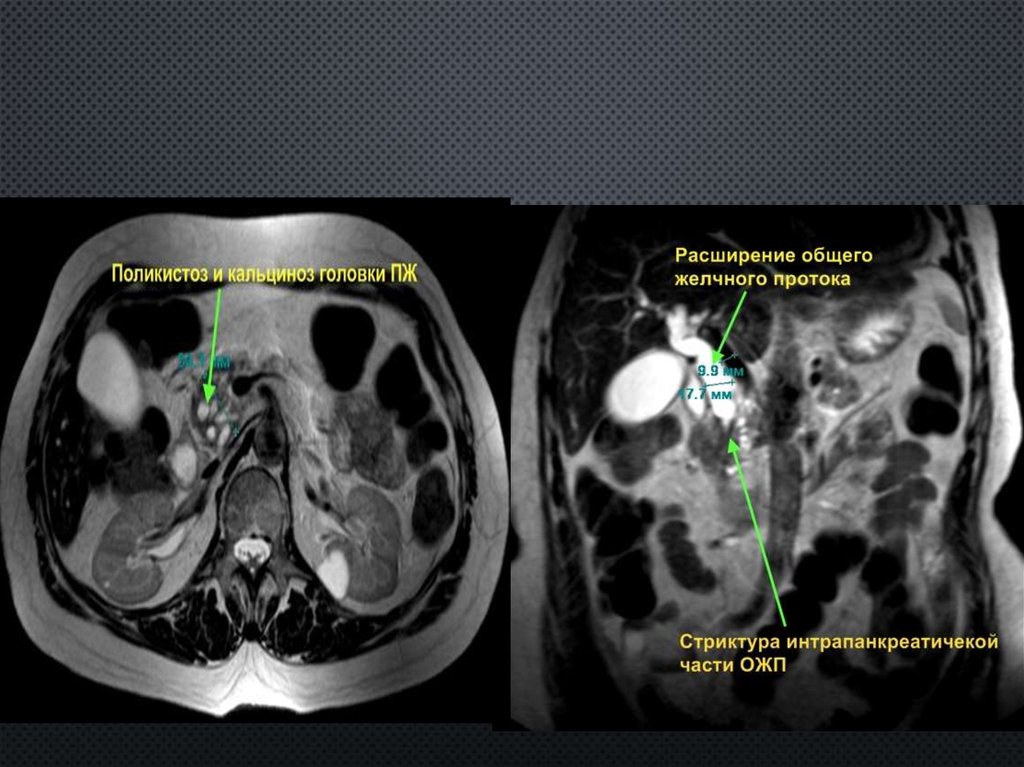

ИНТРАПАРЕНХИМАТОЗНАЯ СУБТОТАЛЬНАЯ

РЕЗЕКЦИЯ ГОЛОВКИ ПЖ +

ПАНКРЕАТОЦИСТОВИРСУНГОЕЮНОСТОМИЯ

ПО РУ